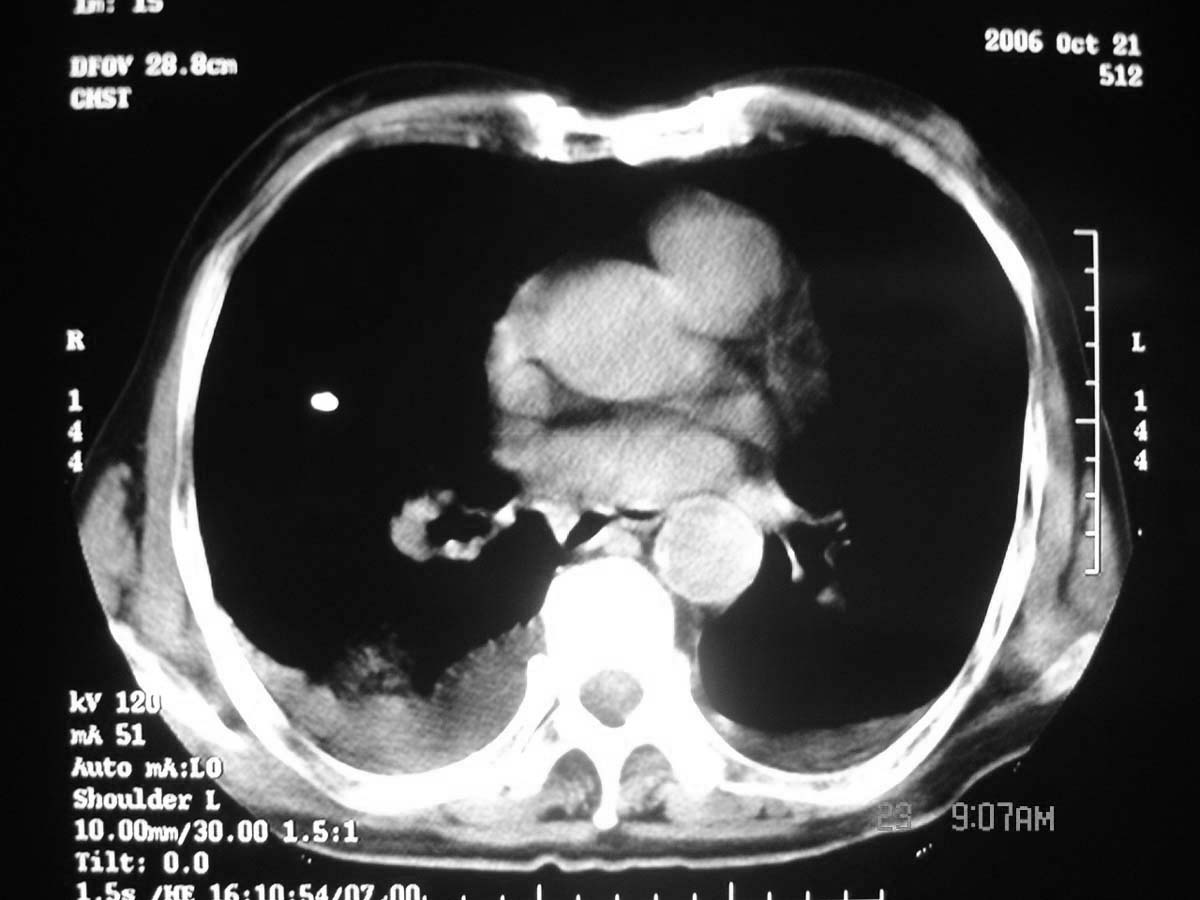

以下是引用守望可可西里在2006-11-23 14:33:00的发言:[br][br] 糖尿病病人很容易继发结核,病人又有双侧胸膜增厚、粘连、胸腔积液以及双上肺的斑片状、条索状影结核病灶影,以一元论考虑,右下肺病变首先考虑干酪性肺炎,可以正规抗炎治疗后复查,排除一般的肺炎。